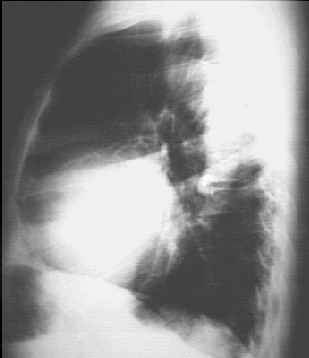

These chest X rays show left ventricular enlargement and a dilated aorta. The PA view demonstrates cardiomegaly, as evidenced by a cardiothoracic ratio greater than 50%. Note also the increased inferolateral cardiac border that is consistent with left ventricular enlargement due to volume overload. The ascending, transverse, and descending aortic shadows are also prominent.

The lateral view shows left ventricular enlargement, as evidenced by posterior displacement of the left ventricular shadow.